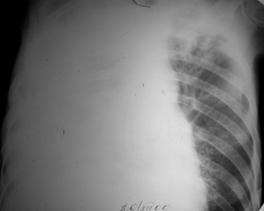

Рис.3. Синдром диссеминации